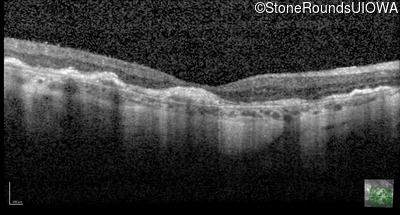

Optical Coherence Tomography - Right - 20/200 +2

Exemplar / OCT Stack